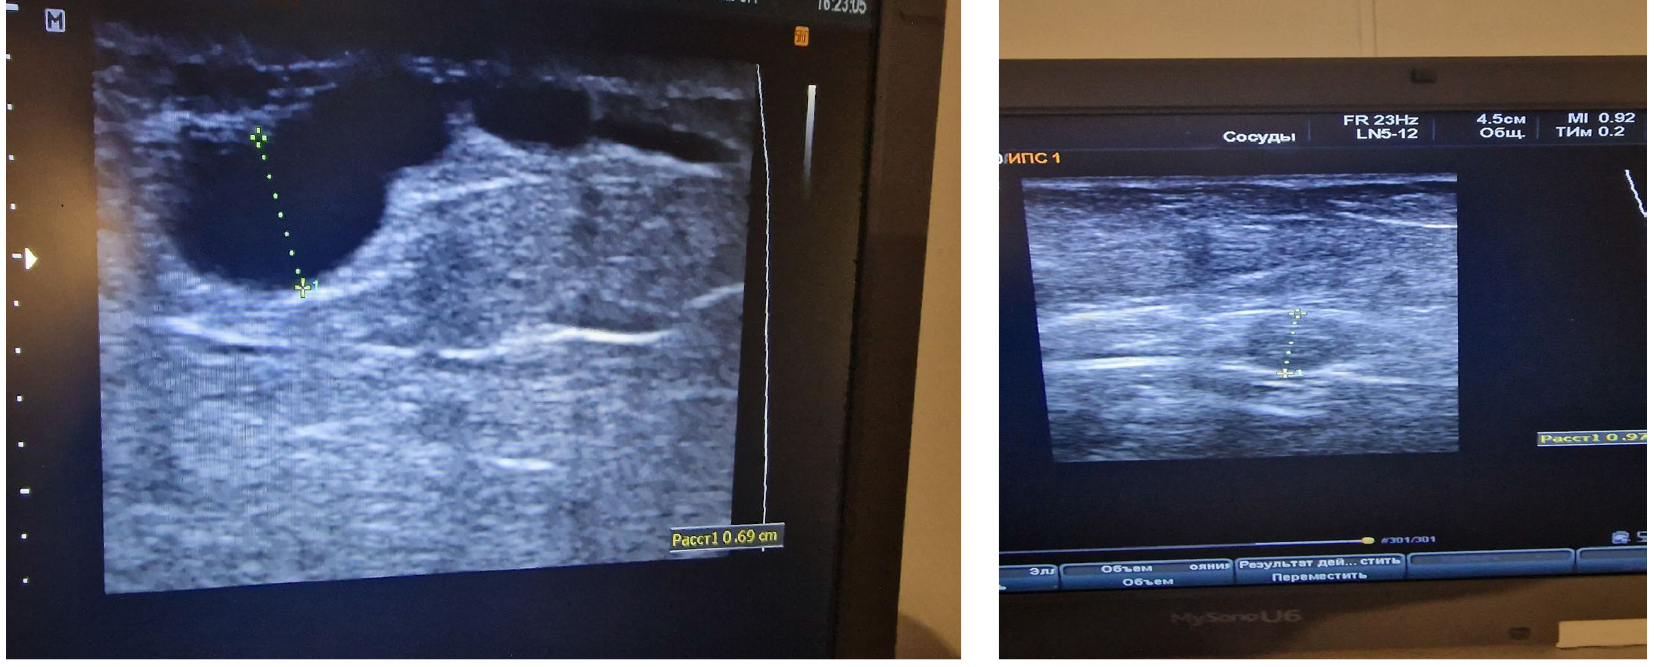

Лечение. В рентгенэндоваскулярной операционной экстренно проведена ангиопульмонография (рис. 2). Была проведена попытка селективного тромболизиса с учетом наличия флотирующего тромба в глубокой бедренной артерии. По данным прямого измерения давления в легочной артерии легочная гипертензия регрессировала, по данным контрастирования проходимость легочной артерии восстановлена. Системный тромболизис не применялся с целью высокого риска повторной тромбоэмболии. Также с целью защиты от повторной тромбоэмболии проведена установка съемного кава-фильтра.

Рис. 2. Ангиопульмонография, картина среднедолевой эмболии в системе правой легочной артерии